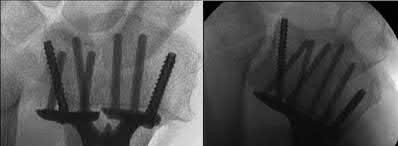

A 30-year-old male sustains a severe midfoot sprain. Radiographs reveal widening between the bases of the first and second metatarsals. The primary ligamentous stabilizer disrupted in this classic Lisfranc injury connects which two osseous structures?

The Lisfranc ligament is the strongest ligament in the tarsometatarsal joint complex. It courses obliquely from the lateral aspect of the medial cuneiform to the medial base of the second metatarsal. It acts as the primary stabilizer of the second metatarsal base. Disruption results in the classic widening between the first and second rays, often with an avulsion fragment ('fleck sign').